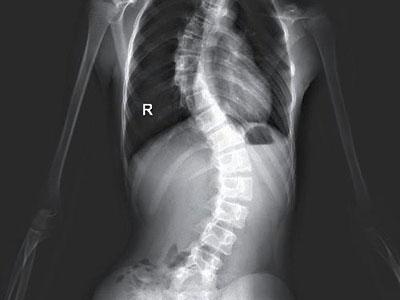

3、关节脱位、半脱位,关节活动度增加、受限,组成关节骨端的畸形等都是引起脊椎畸形的原因。其原因可以是先天性的发育异常格先天性髓脱位人外伤性或病理性(炎症等)脱位,关节的粘连与强直(如感染或创伤),肌肉的挛缩、长期痉挛或者制动等,皮肤或筋膜的挛缩大面积创伤后的痕痕挛缩人神经系统的疾病(大脑性瘫、脊髓的灰质炎后遗症、周围神经损伤、疾病等),另外的原因不明的疾病(特发性的脊柱侧弯等)。